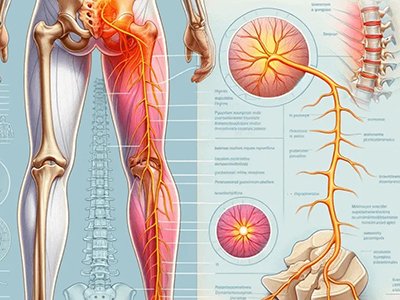

We offer physiotherapy treatments across Neuro/ Ortho/ Chiro/ Pediatrics/ Geriatrics/ Sports related issues covering a wide range of conditions & symptoms